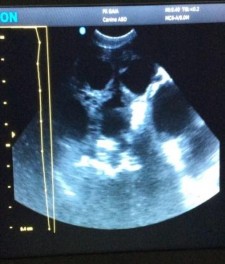

Hình 3.3. Hình ảnh siêu âm sỏi bàng quang

Trường hợp viêm bàng quang, khi siêu âm thấy hình ảnh tiêu biểu nhất là độ dày lan tỏa ở thành bàng quang, bề mặt bàng quang có hiện tượng tăng âm không đều. Trong trường hợp có sỏi bàng quang thì sẽ thấy các hình dạng không đều của các viên sỏi, thấy các khối sinh âm trong lòng bàng quang với bóng lưng sau, các vùng phản âm có kích thước lớn nhỏ khác nhau tùy thuộc vào kích thước của viên sỏi, vùng phản âm này có thể di động và thay đổi vị trí khi di chuyển đầu dò. Nếu sỏi lớn có thể thấy phù lỗ niệu quản, và thành bàng quang dày lên, đôi khi sỏi dính vào thành bàng quang do phản ứng viêm lân cận.

Đối với siêu âm bàng quang cần có nước tiểu trong bàng quang mới thấy rõ được hết, nếu nước tiểu hết thì cho chó uống nước và sau vài giờ siêu âm lại sẽ cho kết quả chính xác.